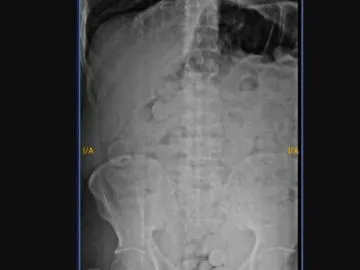

Un interno del Complejo Penitenciario Federal de Jujuy fue internado de urgencia en el hospital "Pablo Soria" de San Salvador de Jujuy tras presentar un cuadro agudo de dolor abdominal. El hombre, de 30 años y oriundo de Salta, confesó haber ingerido más de 180 cápsulas que contendrían marihuana durante una salida transitoria.

En el nosocomio, fue diagnosticado preliminarmente por consumo de sustancias y quedó internado en observación bajo estricta custodia. Según indicaron fuentes oficiales, el objetivo es monitorear la expulsión del material ingerido para su posterior análisis.